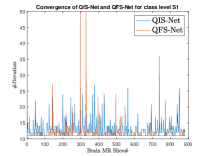

where, represents the true interconnection weight terms of the inter-connection weights as expressed using the Hadamard gate () at an instance (). is a coherent error function of and . Convergence analysis of the proposed qutrit-inspired QFS-Net is provided in Appendix Section -A and demonstrated experimentally with qubit embedded QIS-Net [39] as shown in Figure 3. It can be summarized that the convergence of the QFS-Net is faster than that of the QIS-Net and also follows super-linearity. This claim is also substantiated by the number of iterations required to converge for each image slice in QFS-Net and QIS-Net as illustrated in Figure 4.